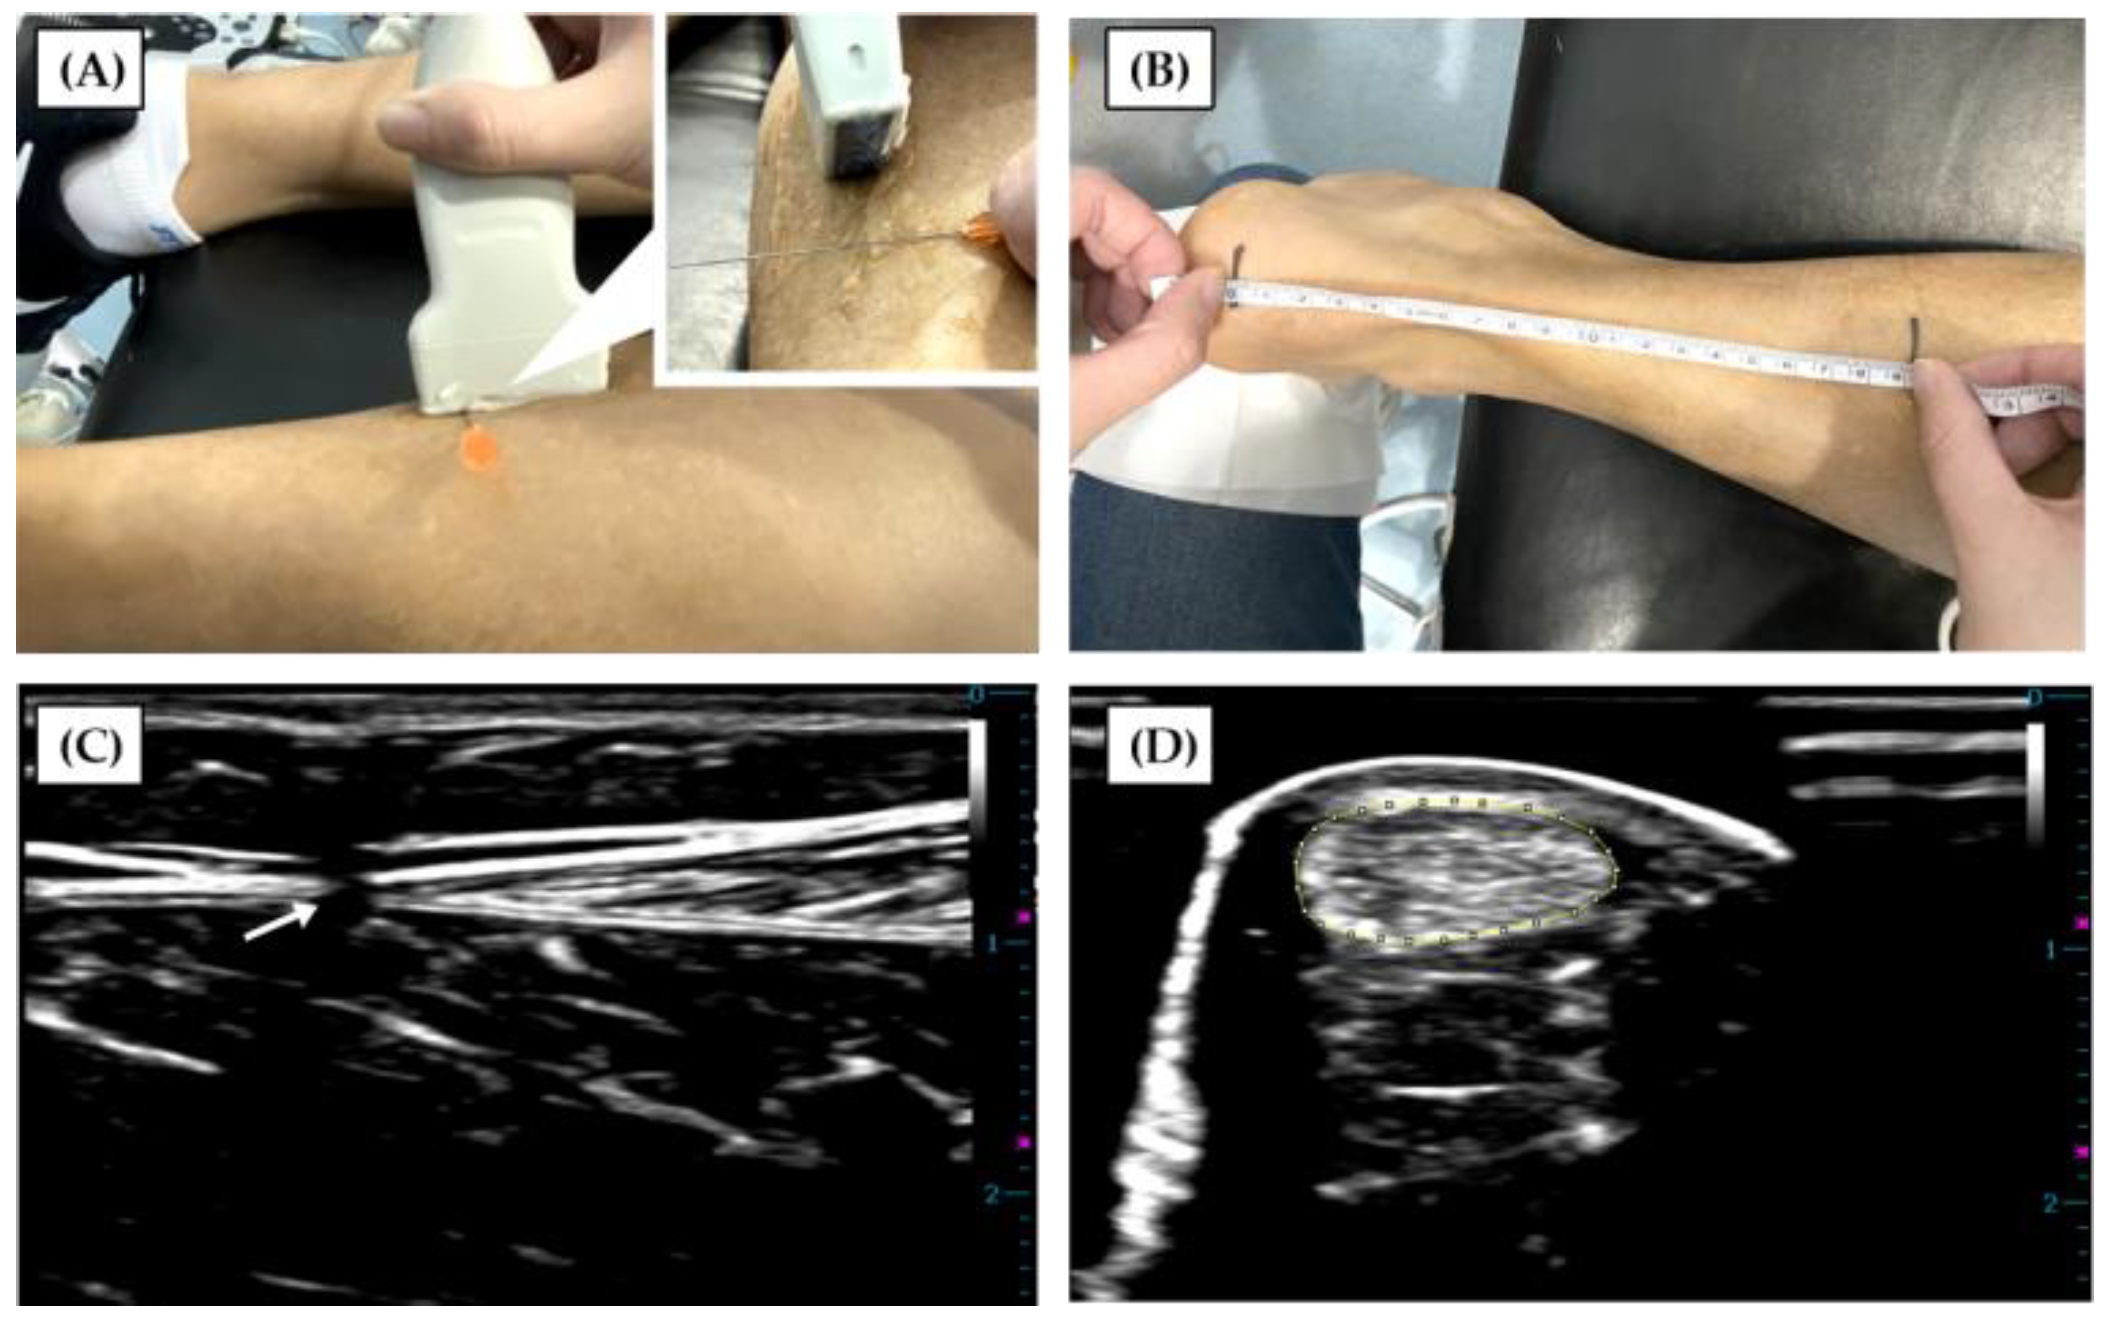

2. Materials and Methods